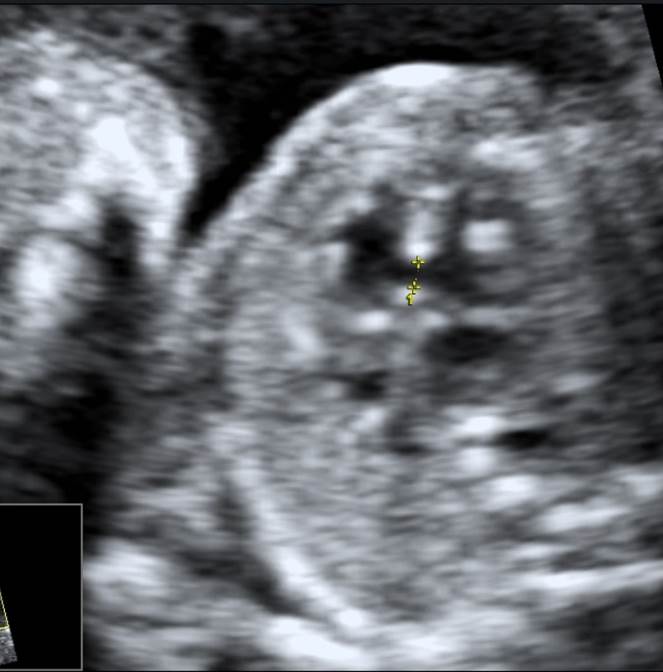

Вопрос 2

1-2.jpg

На какую структуру указывает стрелка?

• А — правое предсердие;​

• Б — левое предсердие;​

• В — правый желудочек;

• Г — левый желудочек

Ответ на вопрос 2